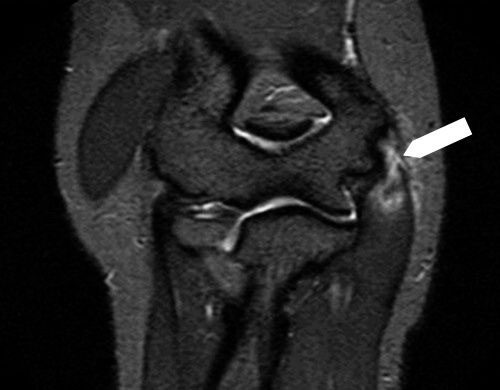

หากสงสัยว่าอาจเป็นโรคอื่นนอกเหนือจากข้อศอกนักกอล์ฟ อาจมีการตรวจเพิ่มเติมเพื่อช่วยแยกโรค โดยการตรวจที่มีประโยชน์มากที่สุดคือ การตรวจเอกซเรย์คลื่นแม่เหล็กไฟฟ้า (MRI) และ การตรวจอัลตราซาวนด์ (อัลตราซาวด์)

ภาพ MRI แสดงภาวะข้อศอกนักกอล์ฟ โดยบริเวณสีขาวที่ลูกศรชี้เป็นตำแหน่งของความผิดปกติ